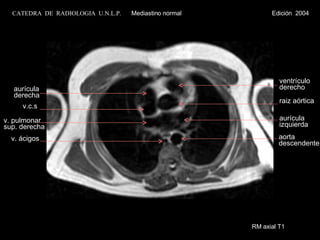

RM axial T1 raiz aórtica ventrículo derecho v.c.s aurícula derecha aurícula  izquierda v. pulmonar  sup. derecha v. ácigos aorta descendente CATEDRA  DE  RADIOLOGIA  U.N.L.P.   Mediastino normal  Edición  2004

RM axial T1raiz aórtica ventrículo derecho v.c.s aurícula derecha aurícula izquierda v. pulmonar sup. derecha v. ácigos aorta descendente CATEDRA DE RADIOLOGIA U.N.L.P. Mediastino normal Edición 2004